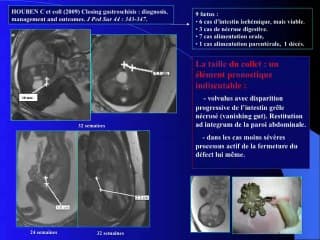

Le Dr Marie Edith Coste nous parle de l'expérience de la région PACA dans le syndrome du grêle court.Ce syndrome du grêle court peut être secondaire à - des atrésies du grêle segmentaire ou multifocale (apple peel syndrome)- à des laparoschisis ou- à des omphalocèlesLe pronostic de ses malformations s'est amélioré grâce au DAN, à la prise en charge précoce en centre spécialisé, avec une meilleure réanimation et une meilleure prise en charge pédiatriquePour cette étude, en région PACA, l'équipe du Dr Coste a croisé le registre des malformations digestives de diagnostic antenatal et le registre des nutritions parentérales à domicile (NPD) entre 2005 et 2015.210 enfants atteints de malformations digestives de DAN dont 81 cas de laparoschisis, 64 cas d'omphalocèle et 65 cas d'atrésie intestinale avec dans l'autre registre 86 enfants en nutrition parentérale à domicile.Les résultats de ce recoupement sont détaillés par l'oratrice8% de mortalité, 30 % d'enfants en NPD pour une durée supérieure à 2 ans et 18% pour une durée supérieure à 4 ans.Attention il existe également des possibilités de syndrome de grêle court post chirurgicaux et/ou avec des troubles de la motricité digestive- les laparoschisis ont été diagnostiqués en antenatal dans 100% des cas, 67 % ont bénéficié d'une fermeture primitive, 57 % n'ont eu aucune complication, le taux de complication augmente avec la nécessité de réintervention. La durée moyenne d'hospitalisation est de 52 jours, et le pronostic est surtout lié à l'ischémie postnatale- les omphalocèles ont dans 50% des cas des malformations associées ou des anomalies chromosomiques, 10% de mortalité post natale, la durée moyenne de séjour est de 35 jours. l'intérêt du DAN est donc la recherche des anomalies associées- l'atrésie de grêle présente 9% de mortalité et une morbidité élevée. La durée moyenne d'hospitalisation est de 32 jours. Elle représente la première cause de nutrition parentérale à Domicile, le diagnostic antenatal est souvent tardif.Au totalLe pronostic des grêles courts s'est beaucoup amélioré, il reste marqué d'une morbidité non négligeable avec des parents pas assez souvent préparés à la longueur de l'hospitalisation